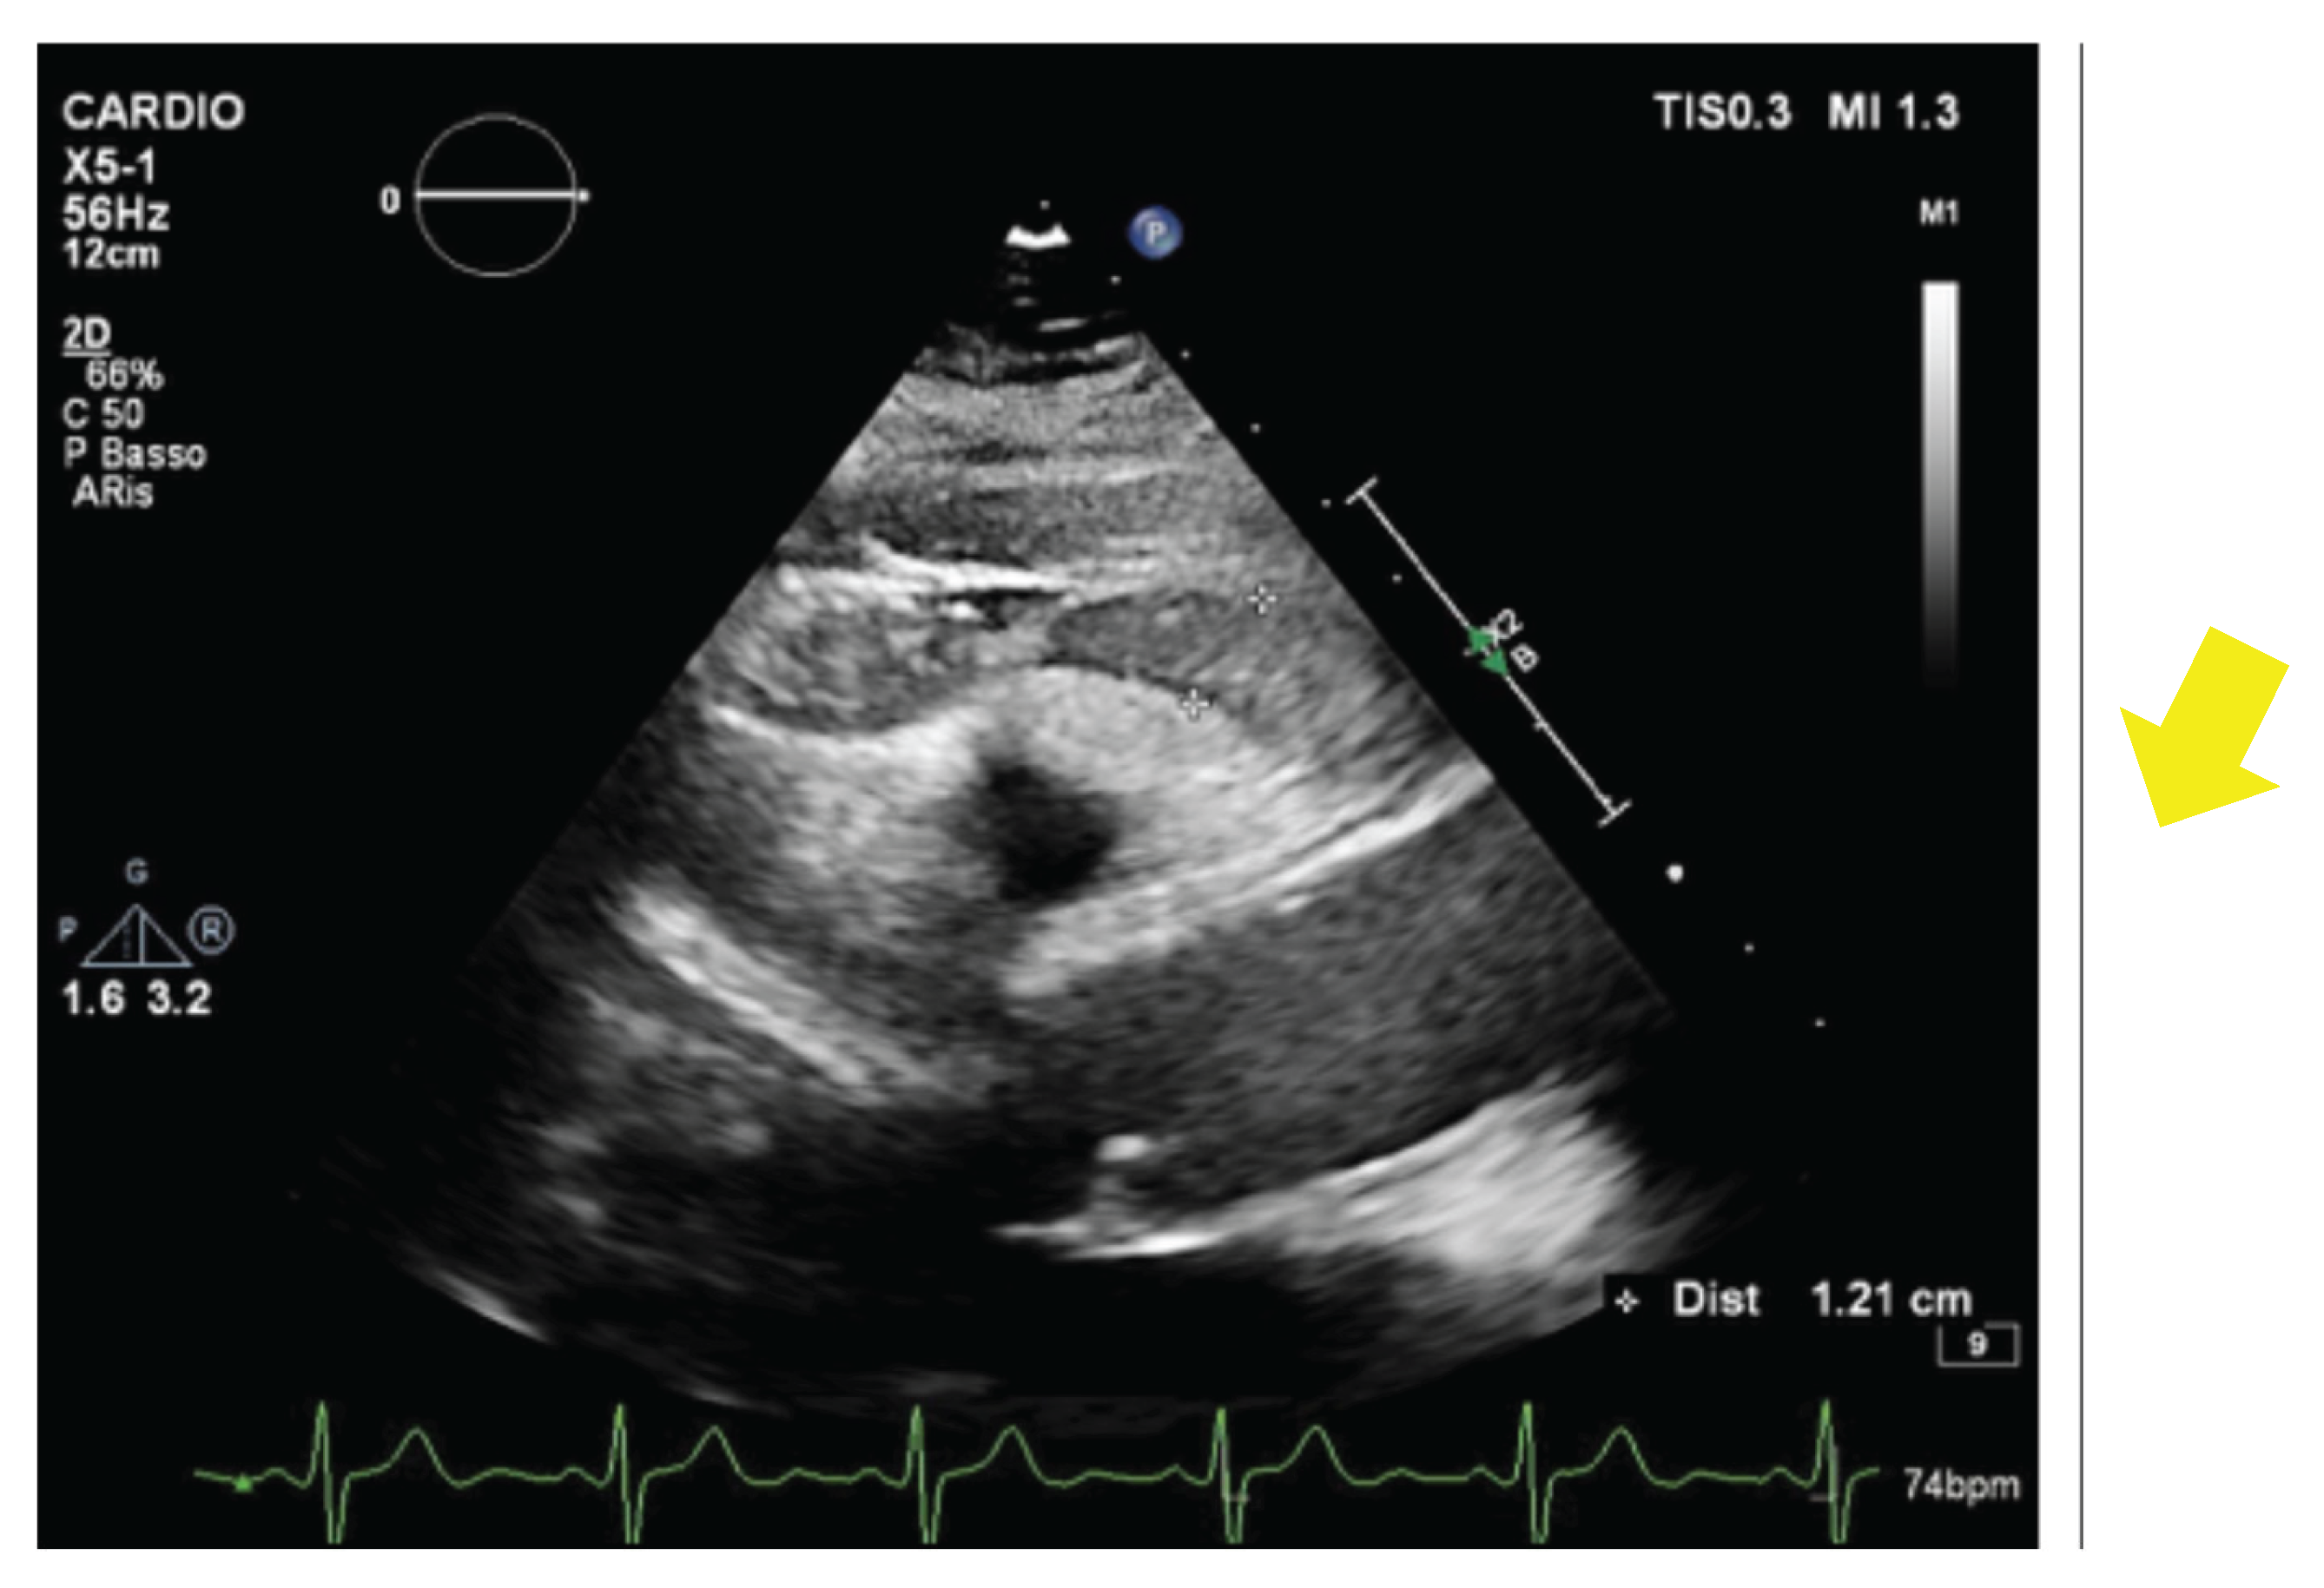

- Eroğlu, S. How do we measure epicardial adipose tissue thickness by transthoracic echocardiography? Anatol J Cardiol 2015, 15(5), 416–9. [Google Scholar] [CrossRef] [PubMed] [PubMed Central]

- Cacciapuoti, F; Caso, I; Crispo, S; Verde, N; Capone, V; Gottilla, R; Materazzi, C; Volpicelli, M; Ziviello, F; Mauro, C; et al. Linking Epicardial Adipose Tissue to Atrial Remodeling: Clinical Implications of Strain Imaging. Hearts 2025, 6(1), 3. [Google Scholar] [CrossRef]

- Cacciapuoti, F; Caso, I; Gottilla, R; Minicucci, F; Volpicelli, M; Caso, P. Left Atrial Mechanics and Remodeling in Paroxysmal Atrial Fibrillation: Introducing the EASE Score for Pre-Ablation Risk Prediction. Med Sci (Basel) 2025, 13(3), 131. [Google Scholar] [CrossRef] [PubMed Central]

- Cacciapuoti, F; Gottilla, R; Caso, I; Crispo, S; Pirozzi, C; Minicucci, F; Volpicelli, M. One size does not fit all: Echocardiography as a decision-making tool in atrial fibrillation management – A case series. J Cardiovasc Echography 2025, 35, 403–9. [Google Scholar]